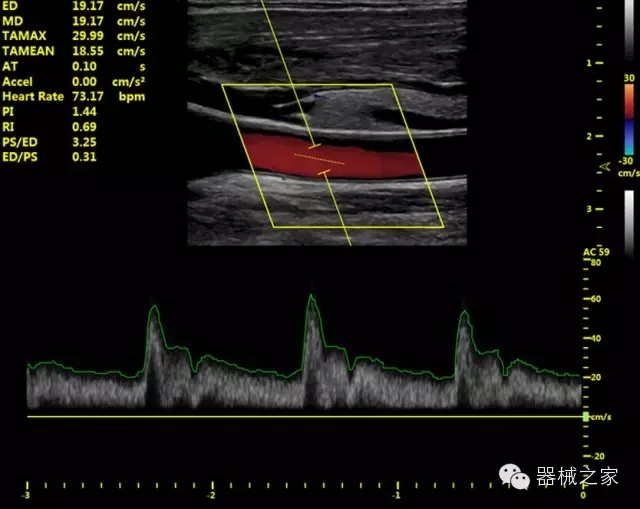

品牌:開立(SONOSCAPE)

公司簡介:

深圳開立生物醫(yī)療科技股份有限公司作為中國民族醫(yī)療產(chǎn)業(yè)的優(yōu)秀引導(dǎo)者,自成立伊始,一直致力于臨床醫(yī)療設(shè)備的研發(fā)和制造,產(chǎn)品涵蓋醫(yī)用數(shù)字超聲診斷系統(tǒng)、電子內(nèi)窺鏡系統(tǒng)、全自動五分類血液細(xì)胞分析儀以及自主研發(fā)的探頭群。

官方網(wǎng)站:www.sonoscape.com.cn

經(jīng)典產(chǎn)品:S8EXP

臨床圖片賞析

產(chǎn)品特點

優(yōu)異的成像技術(shù)

·亞陣元技術(shù):獨(dú)有的亞陣元技術(shù),對獨(dú)立晶片做二次切割,減少旁瓣偽像,增加臨床診斷的準(zhǔn)確性;

·μ-Scan微米成像技術(shù):開立獨(dú)有的μ-Scan技術(shù),還原出真實細(xì)膩、層次對比優(yōu)異的二維圖像;

·倒相諧波成像技術(shù):倒相諧波技術(shù)在去除基波信號的基礎(chǔ)上獲取兩倍二次諧波信號,提高組織圖像的對比分辨力;

·智能微血流成像技術(shù):智能微血流捕捉技術(shù)可以提取出隱藏在背景噪聲中的弱血流信號,大大提高低速血流的敏感性;

全面的臨床解決方案

超聲科常規(guī)領(lǐng)域應(yīng)用

·移植S40高端臺式彩超高端平臺技術(shù),滿足超聲科腹部、淺表、婦產(chǎn)科、心血管、肌骨等應(yīng)用,提供超聲科完美解決方案;

·實時的彈性成像技術(shù):提高了小器管(乳腺,甲狀腺、淺表軟組織腫瘤等)疾病鑒別診斷;

·IMT血管內(nèi)中膜自動測量:為血管性疾病評估提供了有效的評估手段;

·心功能綜合指數(shù)(TEI指數(shù)):用于左、右心室整體心臟收縮舒張功能評估的測量方法;

·全方位可調(diào)M型:有利于更好的觀察心腔大小及室壁階段性運(yùn)動的異常情況;

·組織多普勒成像(TDI):TDI可定量評價心肌運(yùn)動,判斷是否有局部病變,還可評價早期的舒張功能;

·高效3D/4D成像技術(shù):高速的4D幀頻,豐富的3D成像模式,智能斷層切片功能;

POC領(lǐng)域解決方案

·外觀小巧;

·穿刺增強(qiáng)技術(shù):可有效提高進(jìn)針區(qū)圖像分辨率,提高進(jìn)針亮度,全面提高一次性穿刺的成功率;

全面的術(shù)中探頭解決方案

·小凸探頭:開放性手術(shù),實時監(jiān)測病灶位置,提高手術(shù)成功率,可應(yīng)用于麻醉科、肝膽外科、腫瘤外科、神經(jīng)外科、泌尿外科等手術(shù);

·L型線陣探頭:高分辨率圖像,清晰顯示病灶位置,提高手術(shù)成功率,可應(yīng)用于麻醉科、胸外科、肝膽外科、腫瘤外科、神經(jīng)外科、泌尿外科等應(yīng)用;

·MPTEE:經(jīng)食道探頭術(shù)中監(jiān)測,可測量心臟前負(fù)荷(左室舒張末期大小、右房大?。⑿呐叛?、后負(fù)荷、收縮功能、室壁運(yùn)動分析、肝靜脈血流(與中心靜脈壓相關(guān))等,術(shù)后還能及時評估手術(shù)效果評估;

·獨(dú)有的大角度及實時溫控技術(shù),能同一切面顯示宮頸及宮體,有效減低了患者的痛苦,及保護(hù)粘膜保證了醫(yī)療安全;

高效的人機(jī)工程學(xué)設(shè)計

·15‘’高清醫(yī)用顯示器;

·內(nèi)置雙探頭接口;

·可升降臺車,1拖3探頭擴(kuò)展器;

·m-Tuning一鍵優(yōu)化;

CFDA注冊證編號

·粵食藥監(jiān)械(準(zhǔn))字20132230491